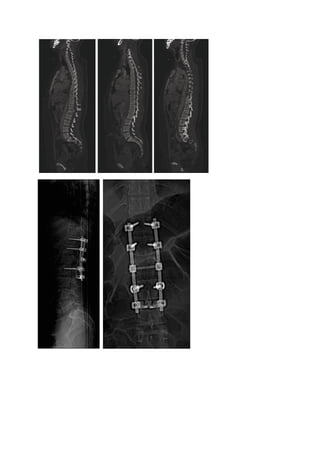

Fractures étagées de

Fractures étagées de L1

T10 à L2 en rotation

(Type                  B)

(Type             C).

Avec           paraplégie

Traitées

sequellaire.

orthopédiquement.

Cyphose      douloureuse,

Aspect de scoliose

lésion cutanée en regard

secondaire         de

du sommet de la cyphose.

sommet T12.